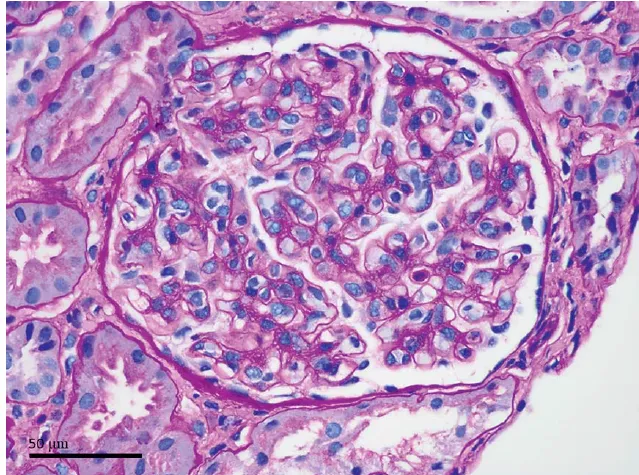

Paciente de 40 anos se apresenta com piora de hipertensão de início recente, há quatro meses ela havia sido submetida à duodenopancreatectomia devido neoplasia pancreática. O rim esquerdo necessitou de deslocamento manual para facilitar a remoção do tumor e otimizar a radioterapia. Uma tomografia computadorizada pós-cirúrgica mostrou uma área ampla de hipoperfusão segmentar na face inferior do rim esquerdo (Fig. 1, seta).

Realizado investigação da atividade de renina plasmática e do nível sérico de aldosterona que foram 8,4 ng/mL por hora e 18 ng/dL, respectivamente. O uso de losartana normalizou a pressão arterial. Imagens subsequentes mostraram evolução para atrofia cortical do parênquima previamente isquêmico (Fig. 1C, seta). Após vários meses, sua pressão arterial voltou ao normal; a losartana foi descontinuada.

(A) Uma tomografia computadorizada pré-procedimento do abdômen e pelve com contraste intravenoso com rins simétricos (seta). (B) Tomografia computadorizada do 6º dia pós-cirúrgico com uma nova região se hiporealce na região inferior polo do rim esquerdo consistente com hipoperfusão/infarto renal (seta). (C) Tomografia computadorizada 5 meses após a cirurgia com atrofia focal do polo inferior do rim esquerdo (seta).

Este caso ilustra o desenvolvimento de hipertensão devido isquemia renal, seguido de restauração da normotensão, após a perda definitiva do parênquima produtor de renina afetado. A hipertensão renovascular afeta 1%-5% da população pacientes com hipertensão. Independentemente da etiologia, **uma queda de pressão de 20 mm Hg distal a lesão que limita o fluxo sanguíneo pode estimular a liberação de renina, potencialmente produzindo hipertensão.**

A hipertensão renovascular é frequentemente causada por estenose aterosclerótica da artéria renal ou displasia fibromuscular; no entanto, outras condições raras que limitam a perfusão aos rins, como a manipulação externa, têm foi descrito, neste caso é apresentado uma causa incomum caso de hipertensão autolimitada causada por manipulação cirúrgica com constrição da artéria renal, a hipertensão foi autolimitada após evolução para isquemia renal completa.